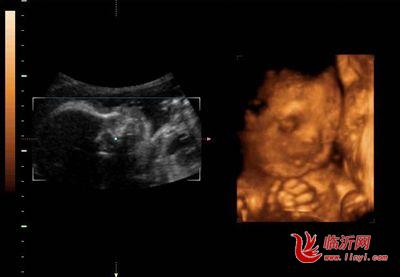

怀孕28周胎儿发育:

这个月的胎宝宝体重已有1100-1400克,坐高约为26厘米,几乎已经快占满整个子宫空间。

他的眼睛既能睁开也能闭上,而且已形成了自己的睡眠周期。有趣的是,他甚至会把自己的大拇指或其他手指放到嘴里去吸吮。这时的胎宝宝活动比较频繁,他会用小手、小脚在你的肚子里又踢又打,有时还会让自己翻个身,把你的肚子顶得一会儿这里鼓起来,一会儿那里又鼓起来。当然,也有的胎宝宝相对比较安静,动作相对少一些。胎宝宝的性格在此时已有所显现,奇妙吧!